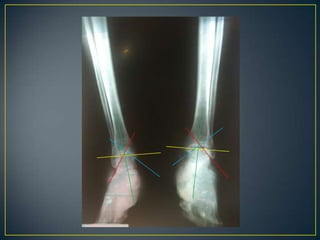

PADECIMIENTO ACTUALInicia el lunes 28 de febrero del 2011 en la tarde, al estar pintando su casa, sufre caída de aproximadamente 8 metros de altura, sin alteraciones de la conciencia, cayendo parado y recibiendo impacto en ambos pies, posteriormente cursa con dolor en ambos calcáneos e incapacidad para deambular, es llevado al servicio de urgencias del IMSS en Altamira donde no puede ser completa su valoración debido a la falta de rayos X, se decide su traslado al IMSS HGR 6 donde es recibido en el servicio de urgencias a las 23:00 horas, se realiza una rx lateral de ambos pies, es diagnosticado por traumatología como fractura multifragmentada de ambos calcáneos, sin lesiones en columna vertebral o cadera, se estable como tratamiento cirugía, se ingresa para su internamiento, sube a piso el 01-03-11 a las 11:45 horas y después se realiza TC la cual confirma el diagnostico antes dado

Diagnóstico: fractura multifragmentada de ambos 	calcáneos 	Tipo III en calcáneo derecho y tipo II según 	Crosby y fitzgibbon y de Sanders

IIIIVVRADIOGRAFÍASSIMPLES 		    TOMOGRAFÍApreoperatoria

II  BTC  preoperatoriaIncongruencia subtalica  post.   :  90 %Conflicto maleolar externo            :  80 %Lesión calcáneo-cuboidea             :  40 %

Crosby y fitzgibbon y de Sanders Tipo I son fracturas no desplazadas. Tipo II son dos partes o dividir las fracturasTipo III son de tres partes o las fracturas de la depresión de división. Tipo IV fueron de cuatro partes o muy conminutas fracturas articulares. Basada en TAC: lesiones complejas